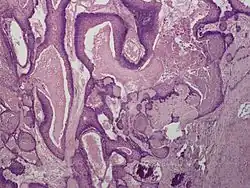

Proliferating trichilemmal cysts (also known as a pilar tumor, proliferating follicular cystic neoplasm, proliferating pilar tumor, and proliferating trichilemmal tumor)[1] is a cutaneous condition, characterized by proliferations of squamous cells forming scroll-like structures.[1][2]: 678

Histologically, Proliferating trichilemmal cysts are distinguished by trichilemmal keratinization, which is the sudden change from nucleated epithelium to anucleated keratinized cells without a granular layer.[4] The differential diagnosis include trichilemmal cyst and Turban tumor.[5]